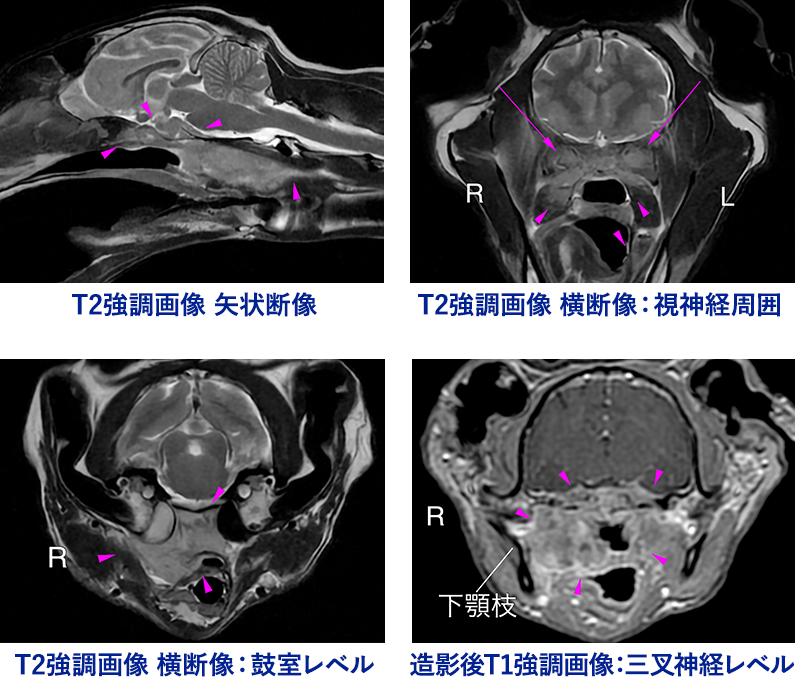

症例3 Mix cat 12歳 避妊メス

<主訴>

3カ月前よりくしゃみをするように

1カ月前より右外耳炎があり、治療反応が悪い

3週間前より食欲低下、瞬膜突出、両目視力消失

1週間前より飲み込みがうまく行かない(嚥下障害)、流涎

<MRI所見>

左右眼窩〜橋レベルの脳底部、右鼓室周囲から鼻咽頭、喉頭背側に続く増殖病変

左右の視神経〜三叉神経の巻き込み、右側舌咽/舌下神経への影響

伴う中耳炎、鼻咽頭の圧排/狭窄